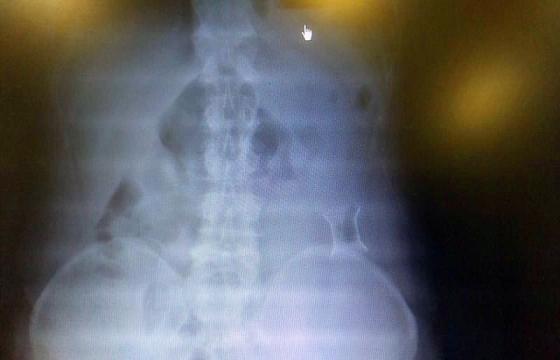

受試患者在結(jié)腸端端吻合術(shù)中,使用我司新研制產(chǎn)品達(dá)到了理想的預(yù)期效果?;颊咝g(shù)后7天、14天X光片顯影,可降解腸道支架均能按研制設(shè)計的預(yù)期時間節(jié)點保持應(yīng)有強(qiáng)度,術(shù)后21天X光片顯示可降解腸道支架已完全破碎,并排出體外。在整個試驗過程中,病患無任何不良反映,耐受良好。